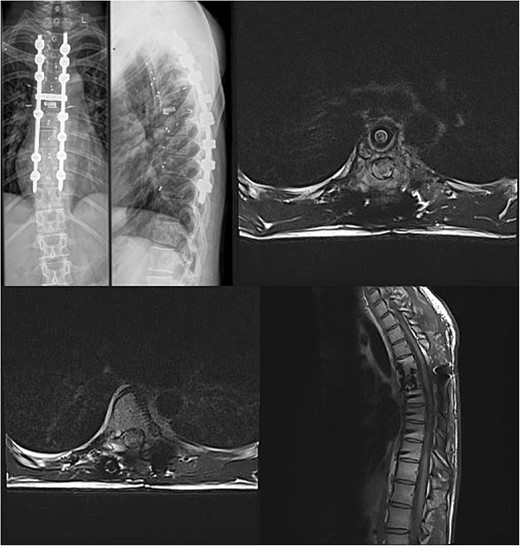

We decided to perform a revision total en bloc spondylectomy at Th6, along with resection of the Th8 pedicle and costovertebral joint, with a partial resection of the adjacent rib. Posterior spinal fixation from Th3 to Th10 was performed using radiolucent carbon screws, and the Th6 body was reconstructed using a radiolucent expandable cage (Figs 3 and 4). During the surgery, MEPs and SEPs were lost, with the patient waking up paraplegic (ASIA score B, VAS pain score 5). Immediate postoperative MRI showed no residual signs of thoracic spinal cord compression due to tumour or haemathoma (Fig. 5). The patient’s neurological status substantially improved the day after surgery, and thereafter, gradually improving over the next few days, allowing the patient to walk independently within 10 days (ASIA score D, VAS pain score 3). A multidisciplinary council decided against postoperative radiotherapy to avoid aggravating neurological symptoms by possibly causing additional damage to the myelopathic spinal cord. On the 11th postoperative day, the patient reported dyspnoea, and urgent CT angiography revealed peripheral pulmonary embolism, which was managed utilizing Deltaparine. Subsequent postoperative course was uneventful, leading to his discharge on the 15th postoperative day, ambulating independently using a walker. MRI follow-up was conducted 6 months postsurgery, followed by yearly checks. At the last follow-up, 2.5 years after the second surgery, there were no signs of tumour recurrence, and the patient exhibited no gait disturbance, back pain, or radiological signs of spinal instability (Fig. 6) (ASIA score E, VAS pain score 0).

Postoperative X-ray imaging immediately after surgery; anteroposterior view (left) and lateral view (right).

Final follow-up X-Ray scan and MRI imaging showing no radiological signs of spinal instability or myelopathy.